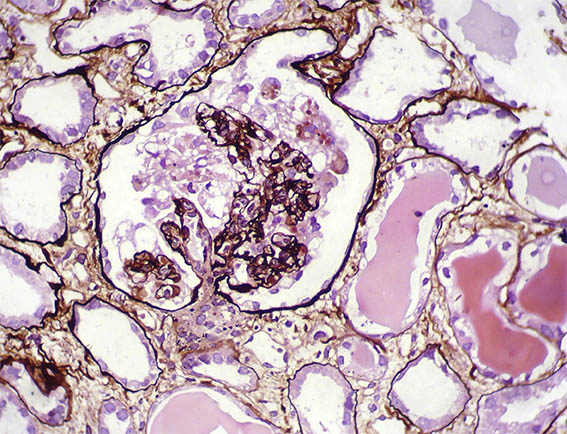

Figure 8. Methenamine-silver, X400.